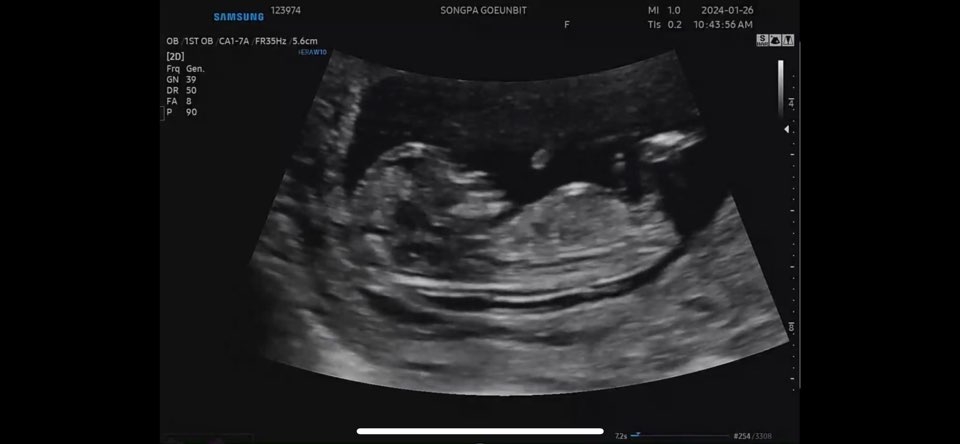

각도법 유명한 곳에서 10주차엔 딸.. 12주차엔 아들인데.. 다들 어찌 보이실까요?? 너무 궁금해요ㅠㅠㅠ